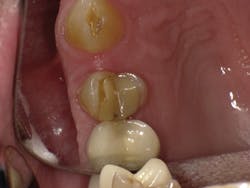

Case Three is a challenging crown repair on a medically compromised patient. The preoperative image shows decay at the buccal margin of an anterior abutment to a bridge (figure 11). Following excavation with the Lite Touch laser (figure 12), we decided to use Futurabond U in a self-etch technique followed by layering Admira Fusion in two increments. The first increment was an opaque layer, using shade OA2 to attempt to block out the gray margin of the porcelain-fused-to-metal crown (figure 13). After light-curing that layer, we applied shade A1 and light-cured and polished the restoration, achieving a highly esthetic result given the difficulty of the situation (figure 14).

Figure 13

Figure 14